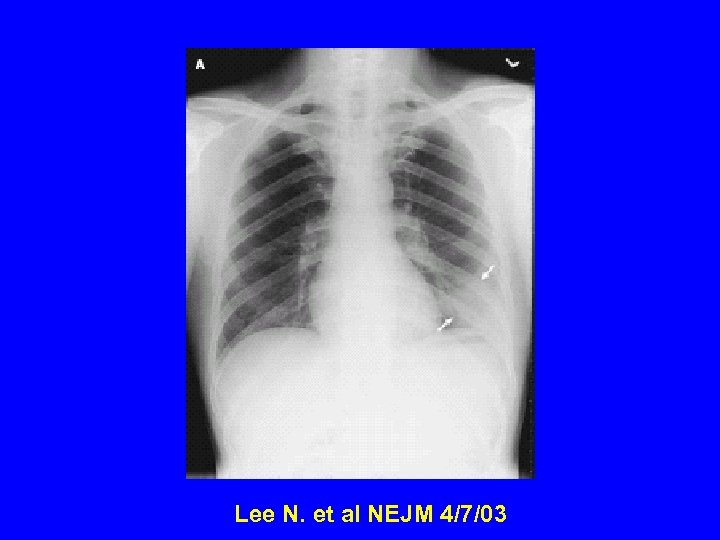

Radiology of typical case Lee NEJM 4/7/04

Radiographic Features of SARS • Infiltrates present on chest radiographs in > 80% of cases • Infiltrates – initially focal in 50 -75% – interstitial – Most progress to involve multiple lobes, bilateral involvement

Lee N. et al NEJM 4/7/03